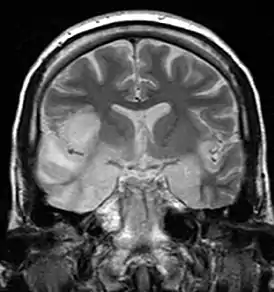

Компьютерная и магнитно-резонансная томография. Также важную роль в диагностике энцефалита играет компьютерная и магнитно-резонансная томография. Они позволяют увидеть очаги поражения в мозгу. Для поиска изменений при энцефалите более информативны результаты магнитно-резонансной томографии. Хотя в начале заболевания изменения на томограммах могут быть незаметны.[26]